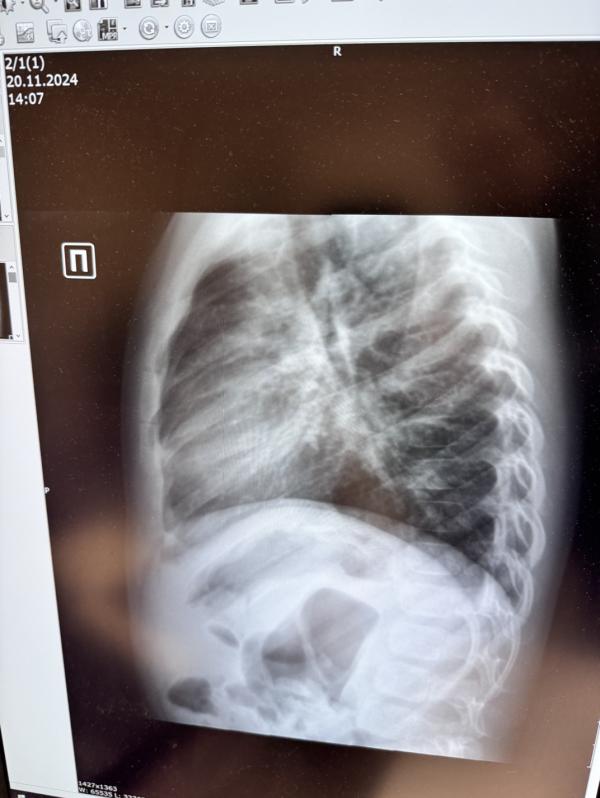

На рентгене увидели это (снимок прикладываю)

Вот в том и дело, обычно течение болезни тяжелое, а тут как-то непонятно, будто снимок вообще не наш

@galka1984, вот я и не понимаю…если бы не снимок, то какая это пневмония